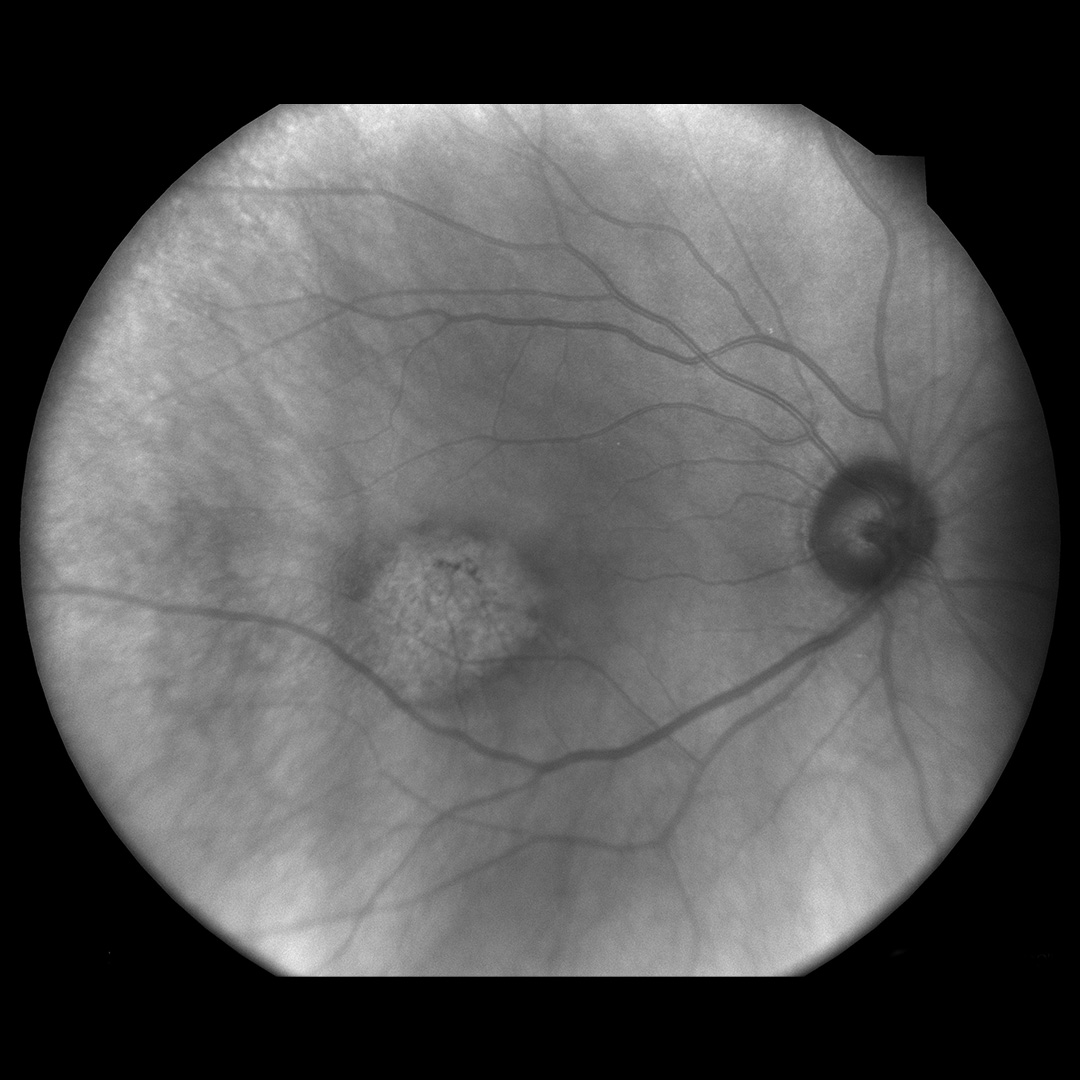

TrueColor Confocal Imaging Examples

High-resolution retinal images captured with the iCare DRSplus — 10 megapixels at 77 pixels/degree, fully automated and non-mydriatic.

Red-free imaging modality

Red-Free

Clinical images courtesy of iCare / Revenio Group. All images captured non-mydriatic.